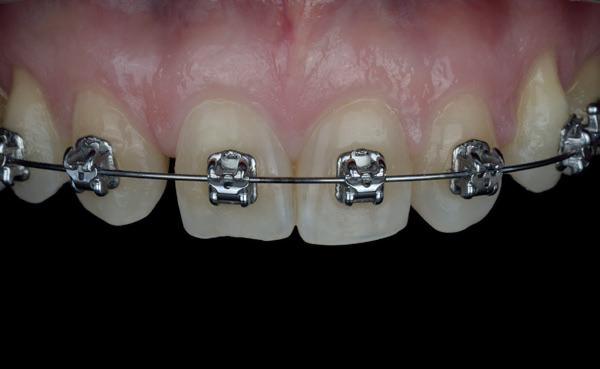

Een 47-jarige vrouw wordt aan het einde van het orthodontische traject door haar eigen tandarts naar mij verwezen voor een intake en eventuele behandeling. Bij mevrouw zijn elementen 12 en 22 afwezig. De 13 en 23 zijn gemesialiseerd. Haar eigen tandarts vraagt of ik het front met composiet kan restaureren om weer een harmonieuze glimlach te krijgen (Afbeelding 1).

Tijdens de intake wordt een complete lichtfoto status gemaakt om de positie van de elementen goed in kaart te brengen en een behandelplan op te kunnen stellen. Op de close-up foto van het bovenfront (afbeelding 2) zien we dat er sprake is van slijtage aan element 11. Elementen 12 en 22 zijn afwezig en elementen 13 en 23 zijn gemesialiseerd. Tussen element 11 en 13 is er sprake van een diasteem. Dit diasteem is niet aanwezig aan de andere zijde (afbeelding 3).

Nadat de vaste apparatuur verwijderd is (afbeelding 7 en 8), zie ik mevrouw voor het maken van een afdruk/scan ten behoeve van een wax-up. Aangezien ik in deze casus wil werken met de injectietechniek, is een wax-up noodzakelijk.

7: Glimlach foto na verwijderen van de vaste apparatuur.

8: Close-up foto van voortanden na verwijderen vaste apparatuur.